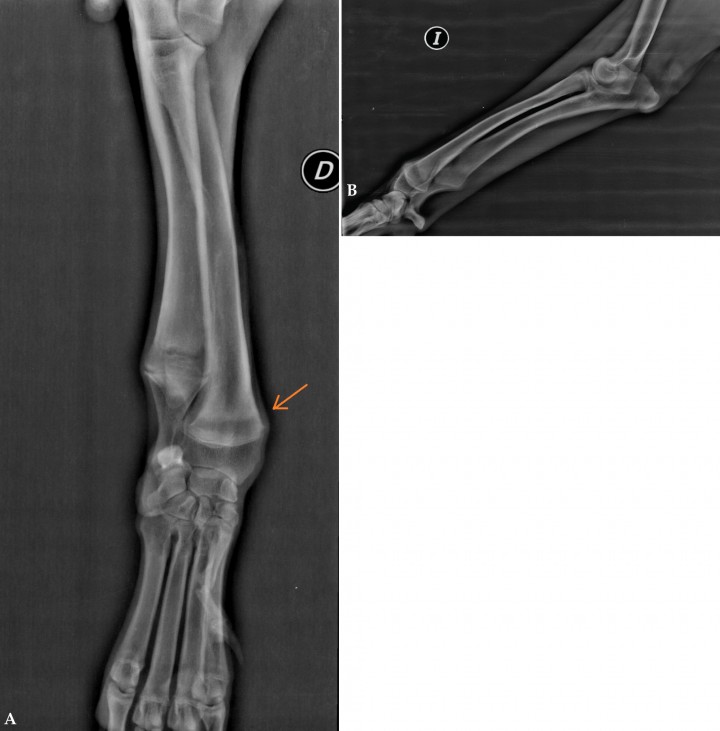

Posteriormente, se llevaron a cabo radiografías de extremidades anteriores y posteriores que revelaron signos típicos de ODH (esclerosis metafisaria, ensanchamiento metafisario y aparición de una línea radiolúcida transversa paralela al cartílago de crecimiento; Fig. 1).

<p>(<strong>A</strong>) Radiografía mediolateral del cúbito y radio del miembro anterior izquierdo. (<strong>B</strong>) Radiografía anteroposterior del radio y cúbito del miembro anterior derecho. Se aprecia la línea radiolúcida en la metáfisis distal del radio (flecha). D: derecha; I: izquierda.</p>

(A) Radiografía mediolateral del cúbito y radio del miembro anterior izquierdo. (B) Radiografía anteroposterior del radio y cúbito del miembro anterior derecho. Se aprecia la línea radiolúcida en la metáfisis distal del radio (flecha). D: derecha; I: izquierda.